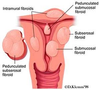

leiomyoma

61

leiomyoma

62

leiomyoma

63

uterine leiomyoma